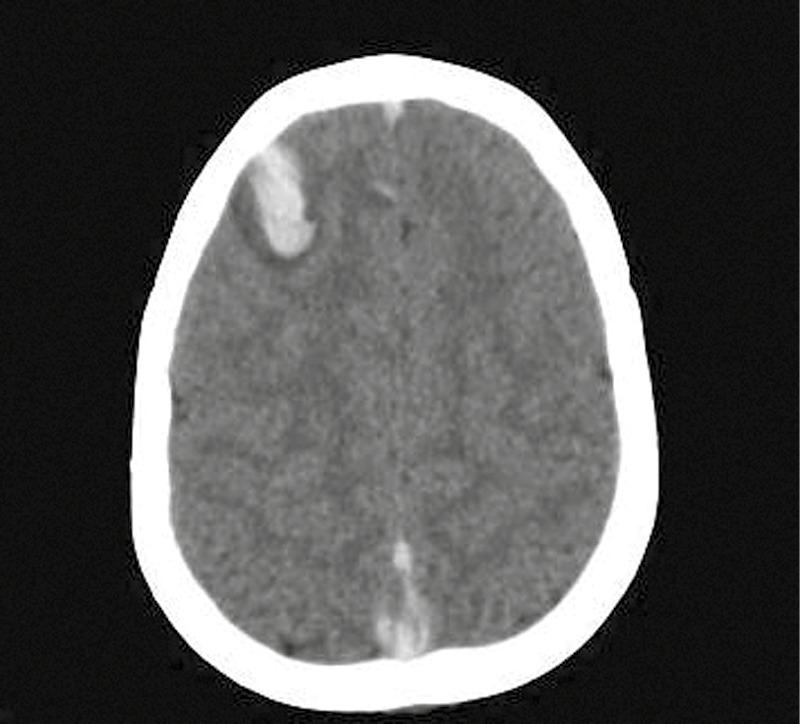

Cerebral venous sinus thrombosis (CVST) is a critical condition with significant morbidity and mortality. It primarily affects the young and healthy. CVST presents a diagnostic challenge due to its varied presentation patterns. We report the case of a 11-year-old boy diagnosed with CVST after presenting with a long history of continuous headache. He improved following anticoagulation therapy. Despite thorough investigation, no discernible underlying cause could be identified.

脑静脉窦血栓形成(CVST)是一种具有较高发病率和死亡率的严重疾病。它主要影响年轻人和健康人群。由于其临床表现多样,CVST在诊断上具有挑战性。我们报告了一例11岁男孩的病例,该男孩在出现长期持续性头痛后被诊断为CVST。抗凝治疗后病情有所改善。尽管进行了全面检查,但未发现明显的潜在病因。